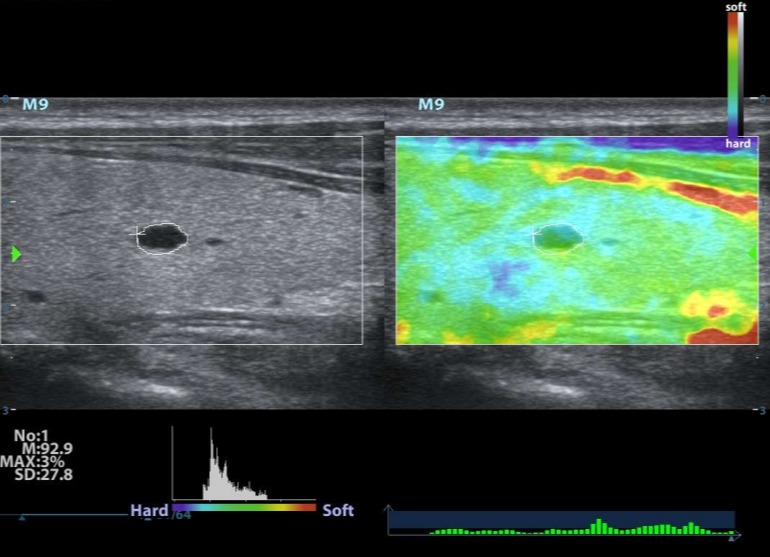

Ecógrafo Mindray M9

Detalles del producto

Características